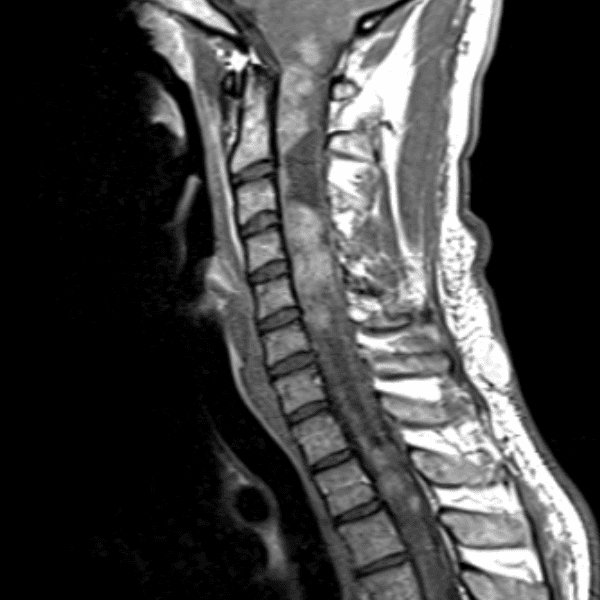

Simulates call by including subtle or difficult cases and some normals.

35 cases